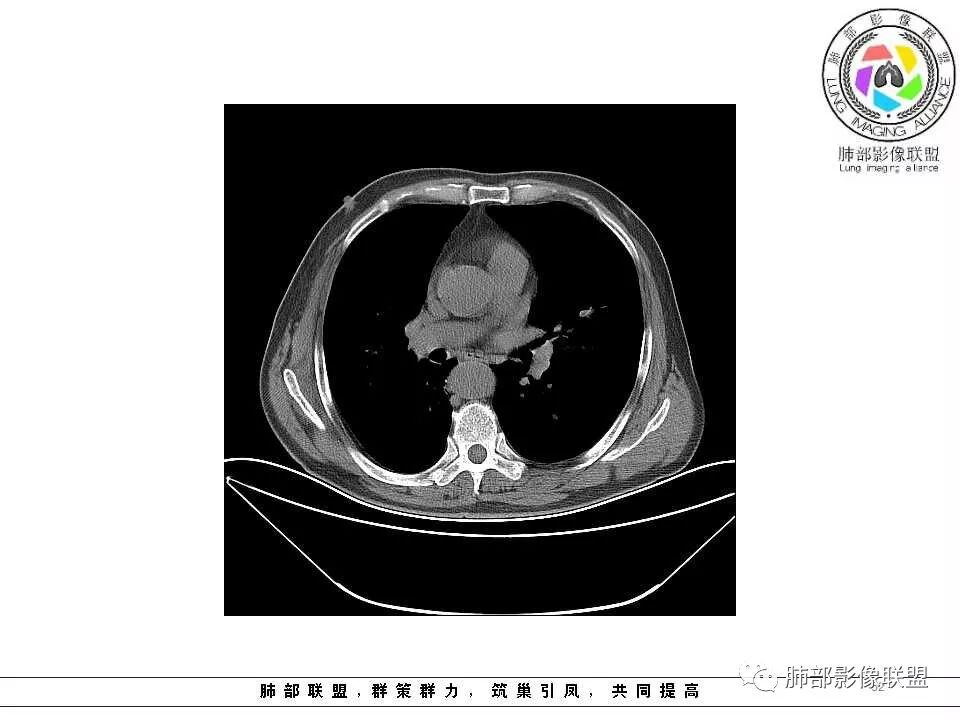

老年男性,两肺可见小叶中央型肺气肿,提示应该有抽烟史。2016年片,右肺门支气管稍模糊,考虑慢性感染,纵膈淋巴结稍大。但2017年左肺上叶新发占位,堵塞支气管,引起局部肺不张伴感染,且纵膈淋巴结较2016年变大,患者同时伴有咯血,考虑恶性。鳞癌?类癌?小细胞?

肺气肿背景,2016年左肺上叶上舌段见微结节,2017年5月左肺结节增大,密度均匀,边缘光滑锐利,与邻近血管关系密切,血管贴壁走行,外侧见尖状突起,下舌段片状影,沿着支气管走行,内有粘液栓,考虑鳞癌,鉴别小细胞肺癌。

肺气肿背景,2016年左肺上叶上舌段见微结节,一年后左肺结节增大,密度均匀,边缘光滑、膨隆,似见小分叶,下舌段片状影,沿着支气管走行,内,老年患者,咯血1月。考虑恶性病变并阻塞性肺炎,鳞癌?注意鉴别结核。

前次片2016年4月20相应位置就有小点状病灶,2017-5-15呈结节影改变,边界膨隆,远端阻塞炎性改变,考虑肺癌,鉴别炎性结节!